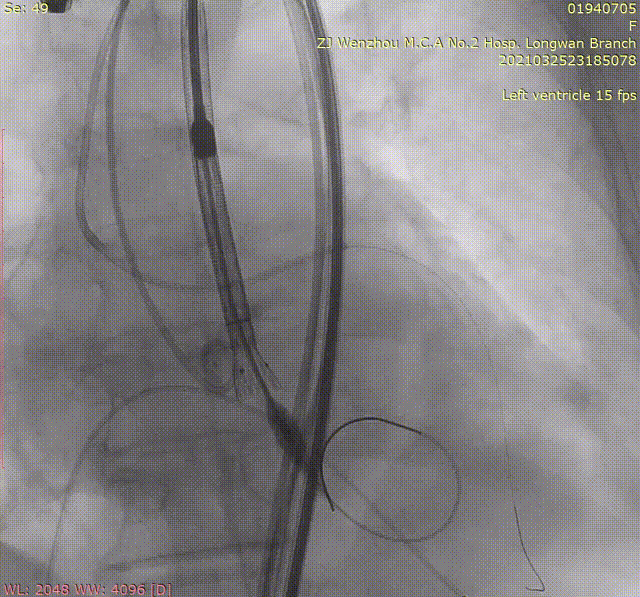

高位释放

释放过程中,造影提示瓣膜出现部分下移,植入位置偏深。为取得更好的手术效果,术者团队当即决定使用VenusA-Plus®的可回收功能对瓣膜进行回收,重新调整释放位置。最终在影像、超声的共同指引下,术者团队通过调整输送系统至最佳位置实现精准释放。

回收后重新定位释放